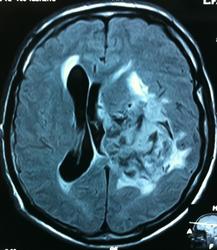

Начало вот здесь http://www.radiomed.ru/cases/kt-gms-obemnoe-obrazovanie-levoi-gemisfery-bolshogo-mozga-vnutrizheludochkovaya-meningioma. Пациент оперирован (меня сначала дезинформировали по поводу операции), перед операцией состояние ухудшилось, возникла правосторонняя гемиплегия, которая осталась и после декомпрессии. МРТ, КТ снимки и выписку предоставила супруга пациента, снимал на iphone, простите за качество, дисков с исследованиями не записывали. Надеюсь вопрос по данному случаю исчерпан.

Вот "цветочки":

T1+C

Т2

FLAIR

Изначально по КТ я так предпологал, а теперь на 100% уверен, разве МРТ это не показало? Гистологически - менингиома, опухоль мозговой оболочки. Покажите, пожалуйста, образование где-нибудь прилежит к костям, где есть мозговая оболочка? Я не вижу, зато отчетливо вижу в левом боковом желудочке из оболочек сосудистого сплетения. Что вас еще смущает? По-моему, предостаточно фактов, чтобы развеять все сомнения.

Мне видится так. Иначе в данной локализации просто неоткуда расти оболочечной опухоли. На контрольной КТ, после декомпрессии, когда срединные структуры стали действительно срединны, правое обызвествленное сосудистое сплетение видно отчетливо, а левое, где оно? Ведь если бы образование компремировало, то после операции, когда часть мозга пролабировало в трепанационное отверстие мы бы увидели и левое сосудистое сплетение, но оно интимно связано с образованием и даже "потянулось" за ним в сторону декомпрессионного отверстия, потому что это и есть "росток" откуда выросла опухоль.